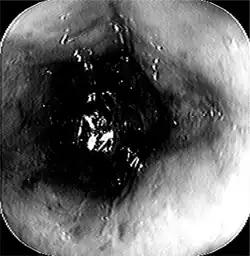

Esophageal disease

Esophageal diseases can derive from congenital conditions, or they can be acquired later in life.